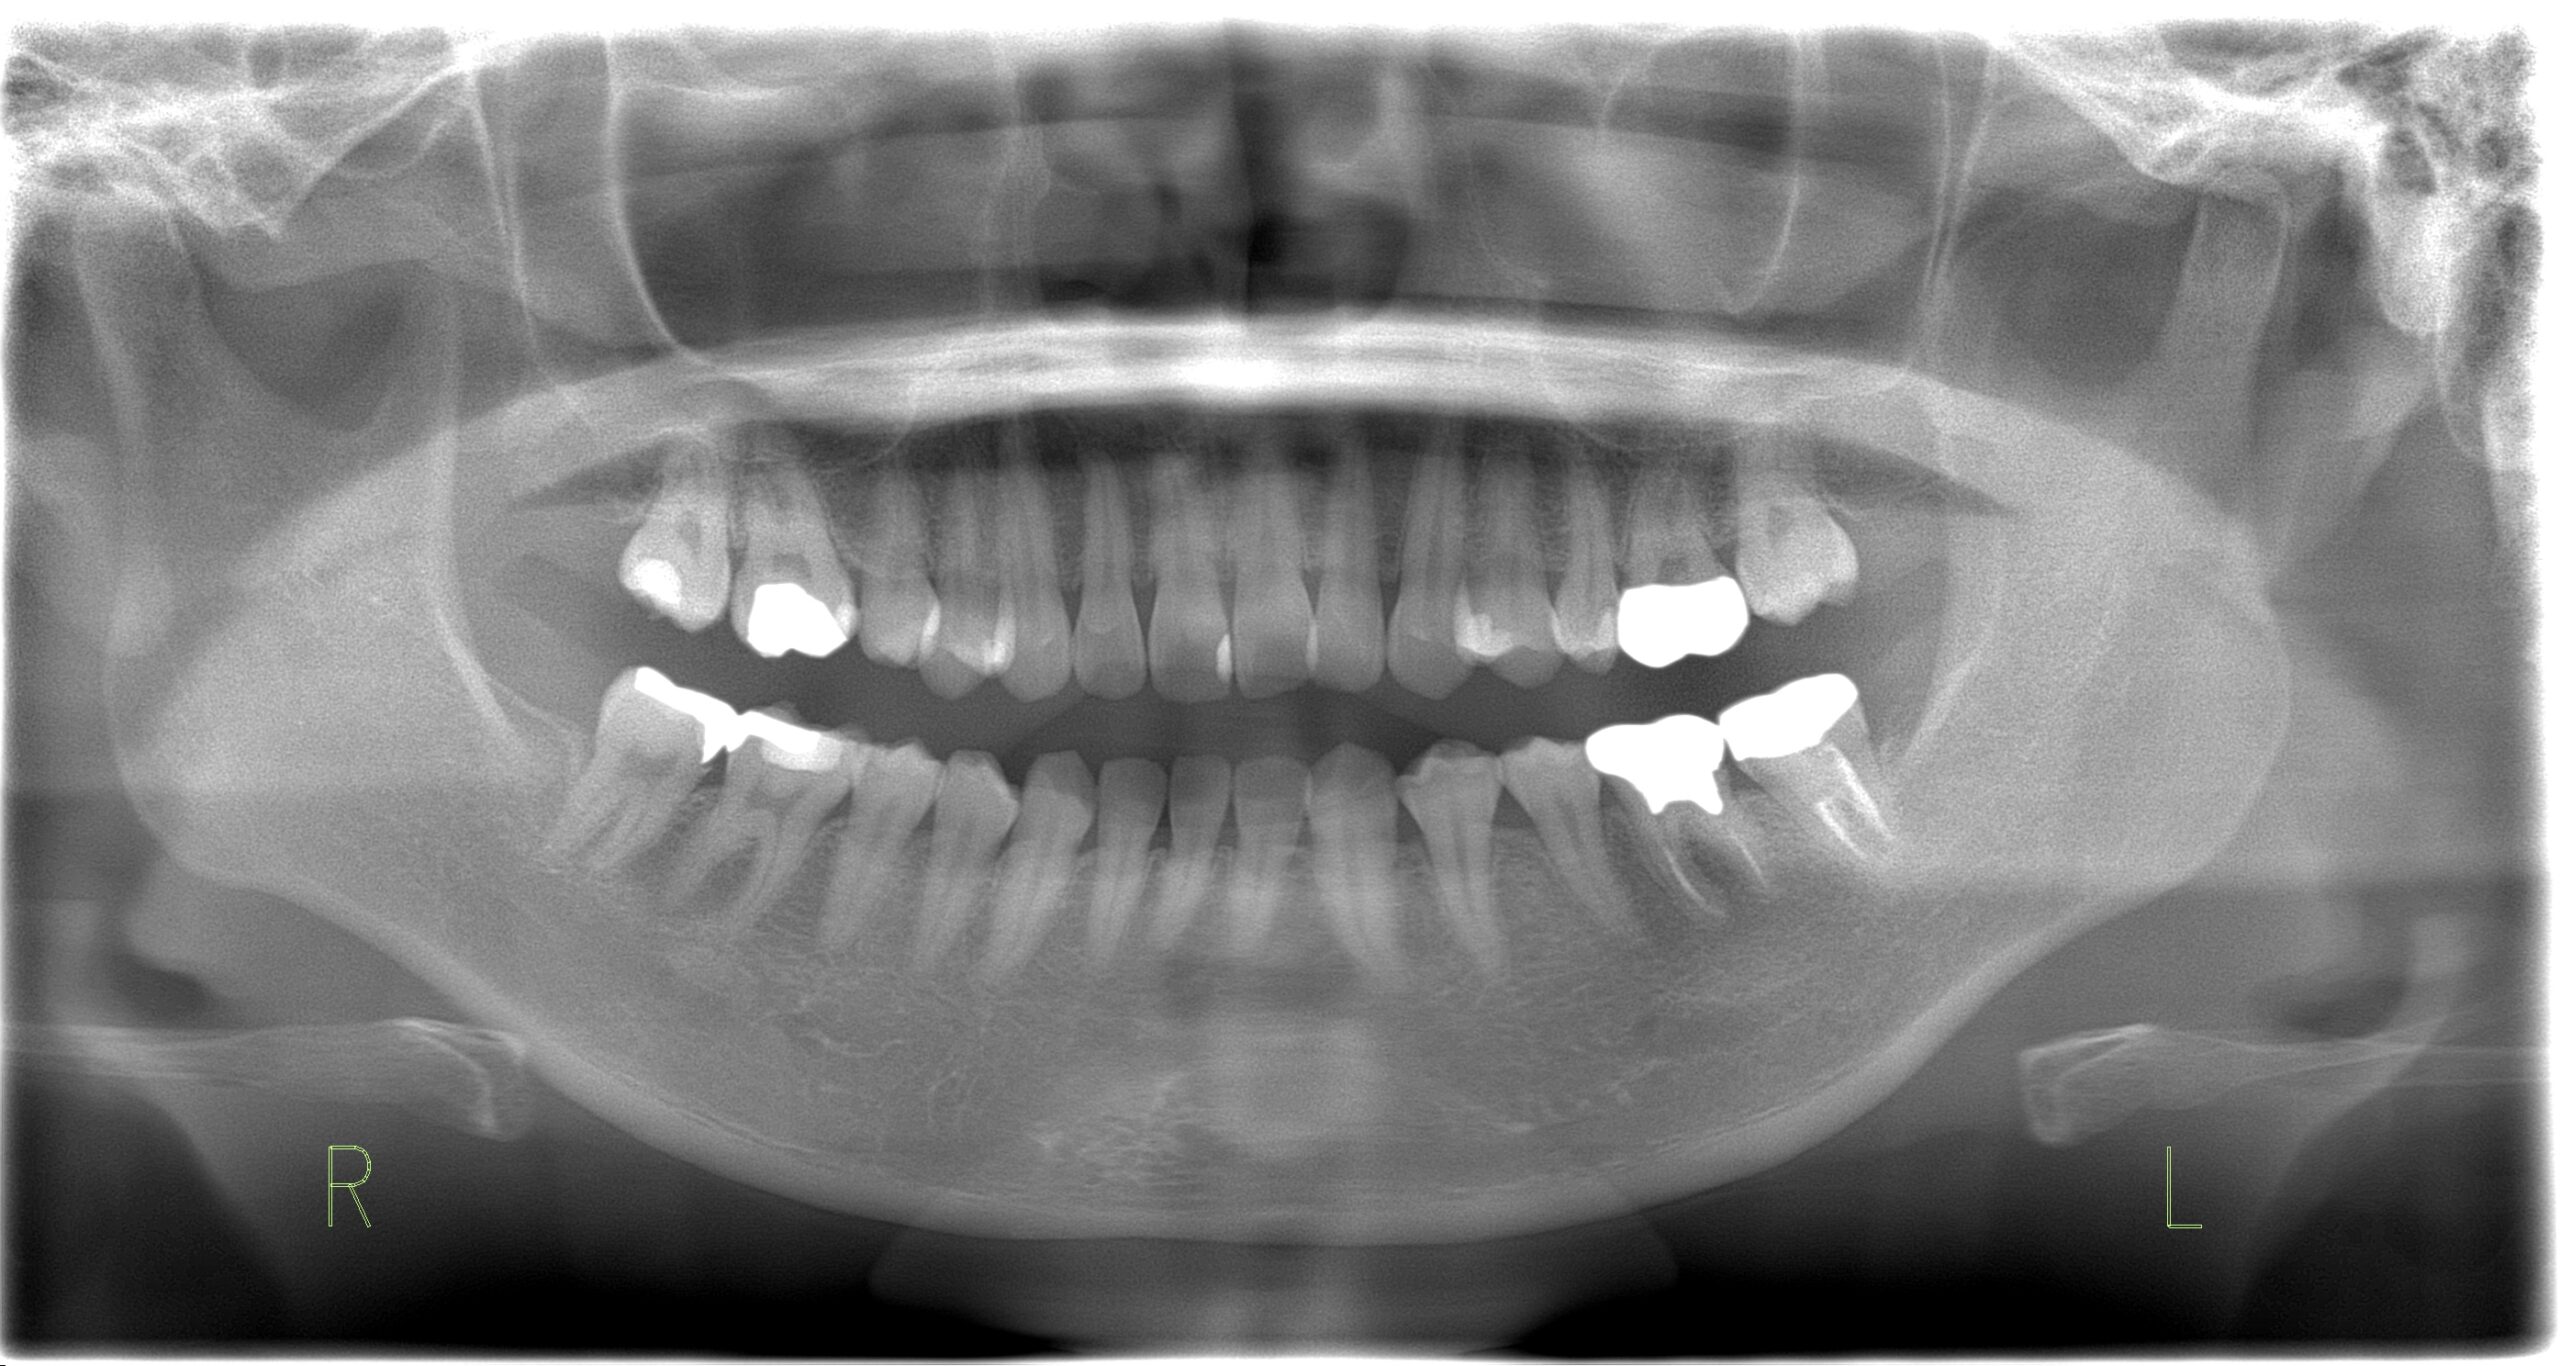

親知らず抜歯

親知らずの抜歯 34歳・男性

Before

-

After

主訴 親知らずを抜きたい 診断名 親知らずの周囲炎 年齢・性別 34歳・男性 治療期間・回数 2か月・4回 治療方法 右下の親知らずは顎の骨の中の神経と近かったのでCTで確認後 抜歯しました。 費用 保険診療 デメリット・注意点 数日間痛み、腫れがでます。 抜歯当日は激しい運動等血のめぐりが良くなることはさけてください。 下顎の親知らず抜歯後は唇、舌にしびれがでることがあります。 -